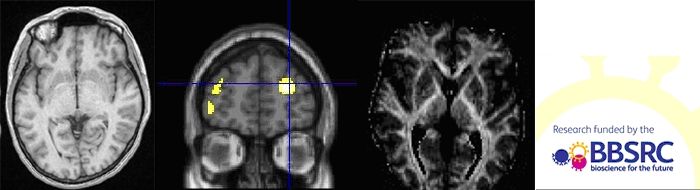

Below are examples of structural images/movies that may reveal important differences between the genotypes.

The movie on the left depicts how the brain is organised structurally, while the movie on the right shows how connections between brain areas (fiber tracts) are laid out.

This programme of research explores these paradoxical findings. Funded by the BBSRC, we are examining cognitive performance in healthy young and mid-aged adult populations. In addition to providing a cognitive profile of e4 population across this wider age range, we are using sophisticated brain imaging techniques to chart the brain activity patterns associated with performance measures in the e4 and non-e4 participants under normal conditions and in response to nicotinic receptor stimulation.